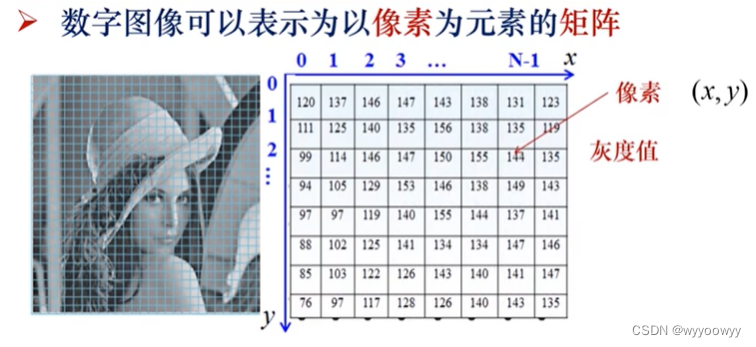

3、图像在计算机表示:

A digital image is defined a 2-D function ,f(x,y)【called intensity or gray level 灰度值】

坐标在计算机中采用的是从左下角到右下角的表达方式

图像用数组表示:(i,j,k,t均为整数)

2D image:f(i,j)

3D image:f(i,j,k)

4D image:f(i,j,k,t)

5、数字图像三要素:

Pixel(picture elements)–像素

Gray level --灰度值

Coordinates–坐标

灰度值:一般表示在0-255的范围内

因为通常使用一个字节表示一个像素,(2^8=256)所以灰阶表示在0-255的范围